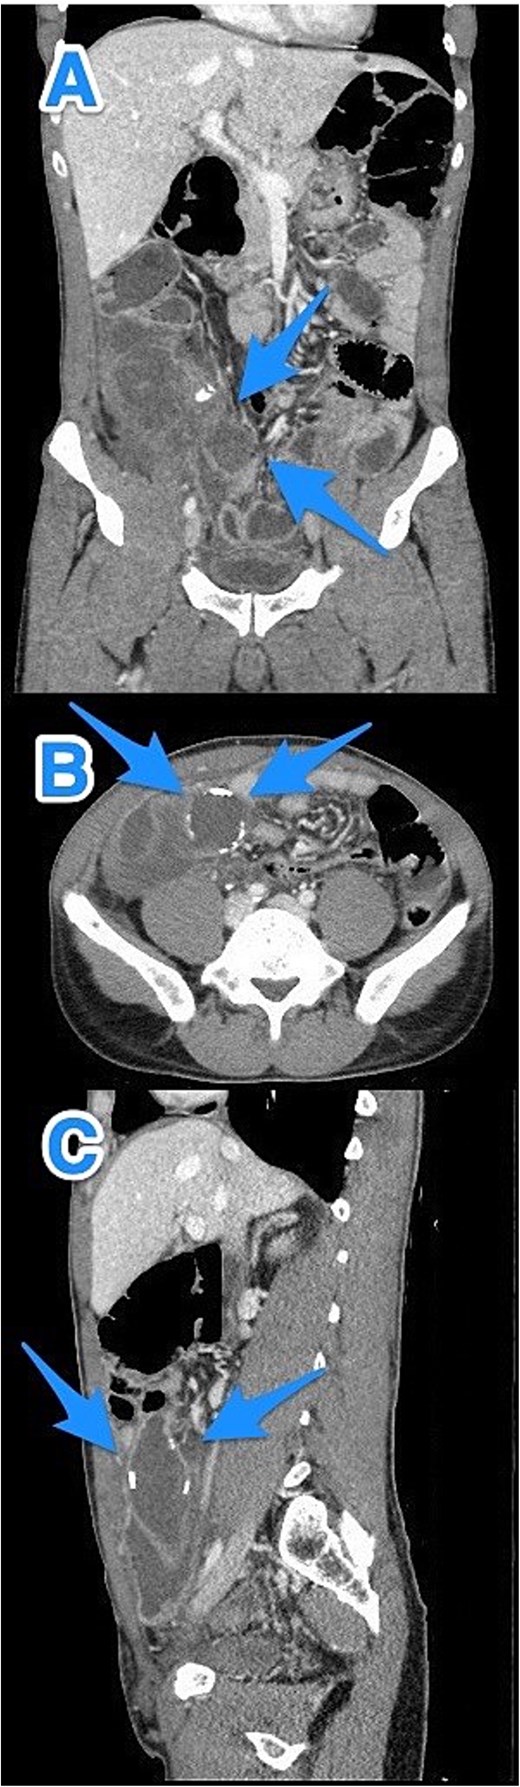

CT abdomen and pelvis with contrast: (A) coronal, (B) axial, and (C) sagittal views demonstrate a dilated, blind-ended structure in the right lower quadrant with incomplete circumferential calcifications and thick fluid content, consistent with an appendiceal mucocele (arrows).

CT abdomen and pelvis with contrast: (A) coronal, (B) axial, and (C) sagittal views reveal an appendix measuring 22 cm in the right iliac fossa, with edematous wall thickening, minimal surrounding fat stranding, and an adjacent fluid collection measuring 3.3 × 1.8 × 8.5 cm, consistent with a perforated appendix (arrows).